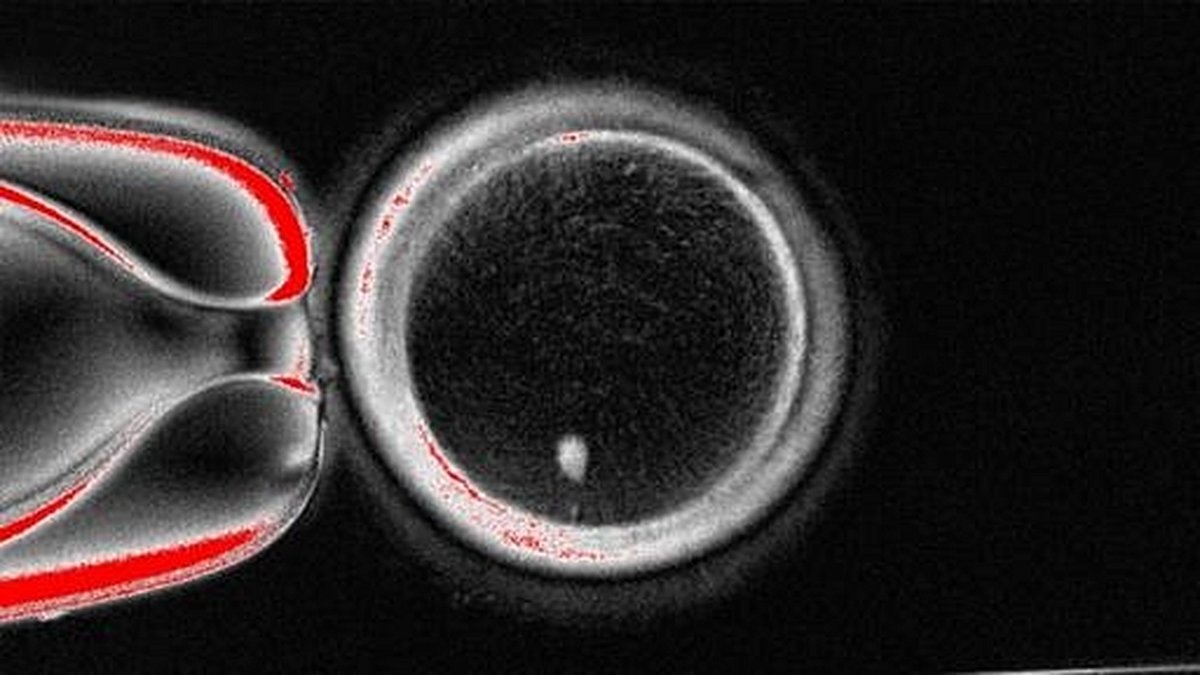

The OHSU team, led by Dr. Shoukhrat Mitalipov, director of the Center for Embryonic Cell and Gene Therapy, employed a method inspired by the cloning of Dolly the sheep in 1997. Rather than relying on the more common approach of converting adult cells into induced pluripotent stem (iPS) cells, the researchers opted for somatic cell nuclear transfer. This involved extracting most of the DNA from a healthy donor egg and replacing it with DNA from a skin cell taken from another person. The resulting egg, now carrying the genetic material of the skin cell donor, was then coaxed through a novel process dubbed “mitomeiosis.” This procedure was designed to mimic the natural reduction of chromosomes that occurs during the formation of eggs and sperm, ensuring that only one set of chromosomes remained.

The researchers produced 82 functional human oocytes, or immature egg cells. Next, these lab-generated eggs were fertilized with donated sperm in petri dishes. The results were cautiously promising: about 9% of the fertilized eggs survived for five to six days, developing to the blastocyst stage—the point at which embryos are typically transferred to the uterus during in vitro fertilization (IVF). As Dr. Mitalipov explained to NPR, “It’s a significant step forward.”